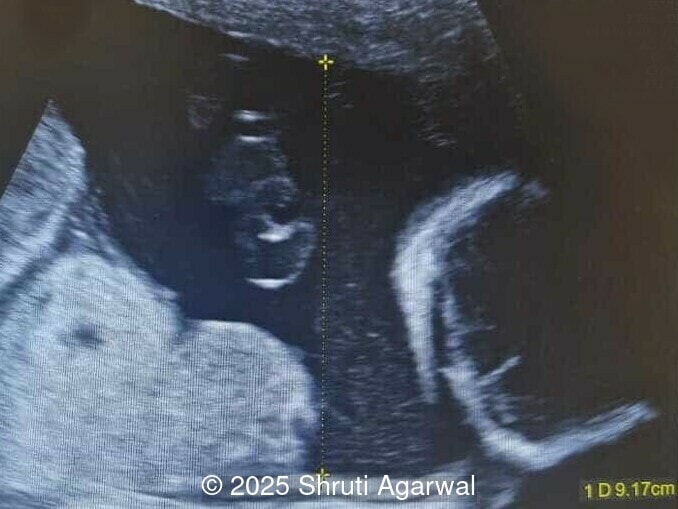

27-year-old primigravid woman presented for ultrasound evaluation at 27 weeks gestation. There was no significant family history or drug exposure during pregnancy. The following findings were observed:

We present a case of fetal anemia due to a giant chorangioma.

• Image 1,2: Large placental tumor is identified with internal vascularity

Placental chorangioma is the most common neoplasm of the placenta occurring in approximately 0.6% of all pregnancies [1]. In most cases, the tumor is less than 5cm in size and asymptomatic [2]. Chorangioma is considered a hamartoma or hyperplastic capillary lesion rather than a true neoplasm due to its inability to metastasize, and the tumor has no malignant potential [3]. Chorangiomas are usually found in the third trimester as a solitary nodule in the placental parenchyma. On gross examination, the chorangioma is well-circumscribed, without a fibrous capsule, and sharply demarcated from the surrounding placental parenchyma by a single or double layer of chorionic epithelium. It tends to have fleshy, congested, red to tan colored surface [4]. The most common location is in the fetal surface of the placenta, in proximity of the umbilical cord insertion. A larger tumor is usually attached to the chorion, which is a less perfused area. A few cases have been reported on the maternal surface, replacing the whole or some part of the placental lobe [4,5]. Chorangiomas tend to arise in areas of hypoperfusion. A hypoxic state is thought to lead to active proliferation of connective tissue and growth of villous capillaries mediated by vascular growth factors [6]. Pre-eclampsia, high-altitude, and fetal anemia have been associated with chorangioma, suggesting that decreased oxygen tension may play a role in the pathogenesis [7,8].

Prenatal diagnosis depends on ultrasound, however, chorangioma can cause an increase in maternal serum alpha-fetoprotein [3]. Ultrasound examination reveals a hypo- or hyperechoic, well-circumscribed mass, which is usually located underneath the chorionic plate near the umbilical cord insertion, and often protrudes into the amniotic cavity. Color Doppler demonstrates large vascular channels around and within the tumor [6,9]. In cases of giant chorangiomas, echocardiography should be performed to assess cardiac function and measure fetal middle cerebral artery peak systolic velocity for diagnosis of fetal anemia. Regular ultrasounds with Doppler studies are used to monitor tumor size, fetal growth, amniotic fluid volume, and signs of fetal anemia or heart failure. The frequency of exams is based on tumor size and associated complications. With small tumors, assessment may occur every 3-4 weeks, whereas in large tumors, the ultrasound scan may be done every 1-2 weeks [3]. These regular assessments can diagnose conditions that require intervention, such as polyhydramnios, hydrops, or hemolytic anemia.